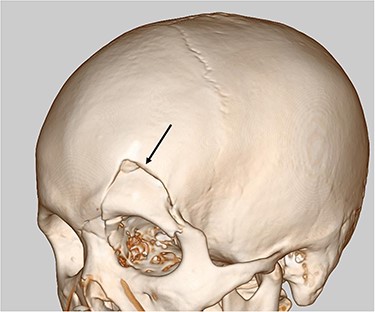

Our case was a 22-year-old man measuring 180 cm in height and weighing 86 kg. Two hours after eating a large amount of food, he was involved in a collision between his motorcycle and a motor vehicle. At the examination, he was alert and his vital signs were stable. The patient presented with an open skull fracture on the left forehead and described muscular defense throughout the abdomen. A whole-body computed tomography (CT) scan showed an open skull fracture reaching the left skull base (Fig. 1), and free air, ascites fluid, disruption of the gastric wall and a large amount of food residue behind the spleen (Fig. 2 and b). The head wound was first treated, and then, a laparotomy was performed on suspicion of a traumatic gastric rupture.

(A) CT scan of abdomen showed free air, ascites (thin arrow) and a large amount of food residue behind the spleen (thick arrow). (B) CT scan of abdomen showed disruption of gastric wall (arrow).